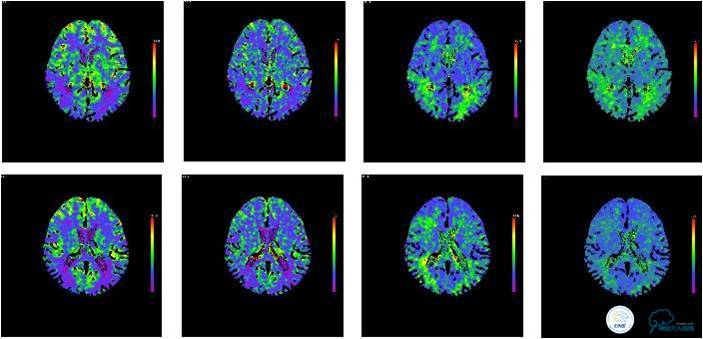

患者入院后,完善颅内CTA(图1)及血管造影(图2~3)检查,发现右侧颈内动脉颅内段闭塞,右侧大脑前动脉依靠左侧颈内动脉系统通过前交通动脉供血,右侧大脑中动脉供血区则依赖于右侧大脑前动脉(ACA)软脑膜代偿供血,左侧大脑中动脉闭塞,依靠一少见血管代偿供血,该血管起自左侧大脑前动脉A2段起始部,代偿供应左侧大脑中动脉供血区。由于该患者灌注CT(图4)未见明显低灌注区,遂给予患者抗血小板、降脂及控制危险因素治疗出院。出院后电话随访未再出现过上述症状。

图4:患者入院后灌注CT提示未见明显低灌注区域。

综上所述,这是一例少见的大脑中动脉闭塞后由RAH代偿供血的病例,由于患者的灌注CT显示灌注尚可,暂时未对患者进行外科干预。